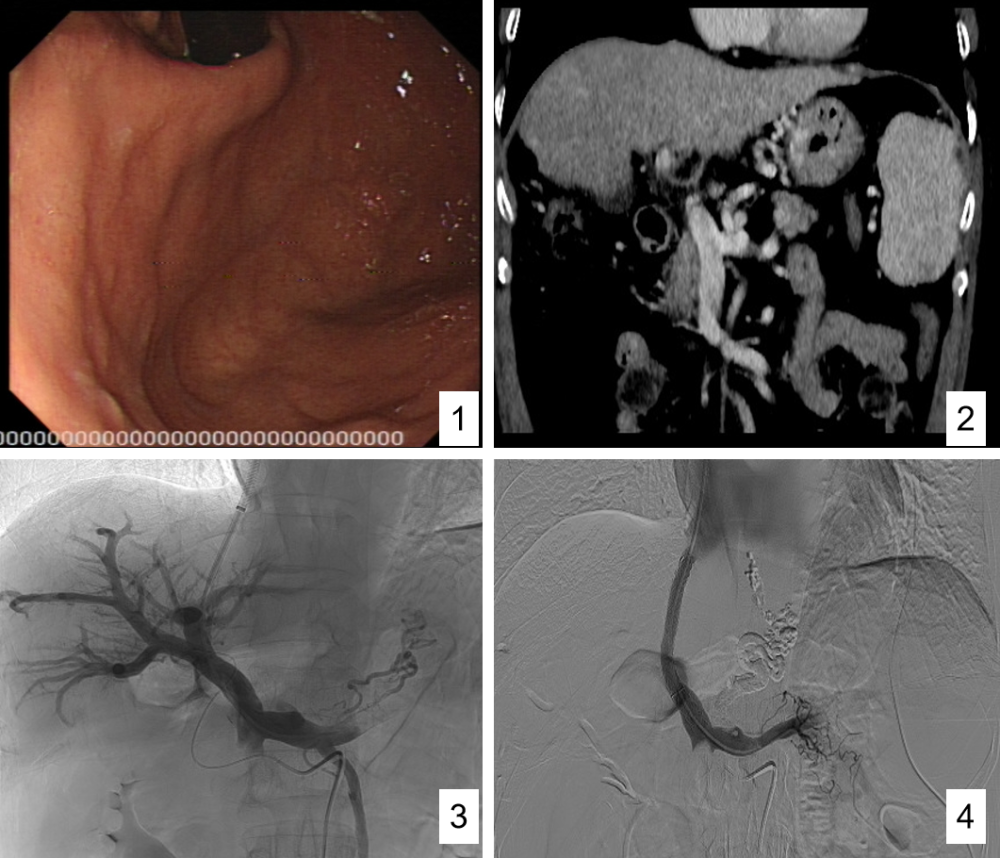

病例1(tipss 胃-食管曲张静脉栓塞术)46岁男性患者,因"突发呕血600ml"

图片尺寸1000x858